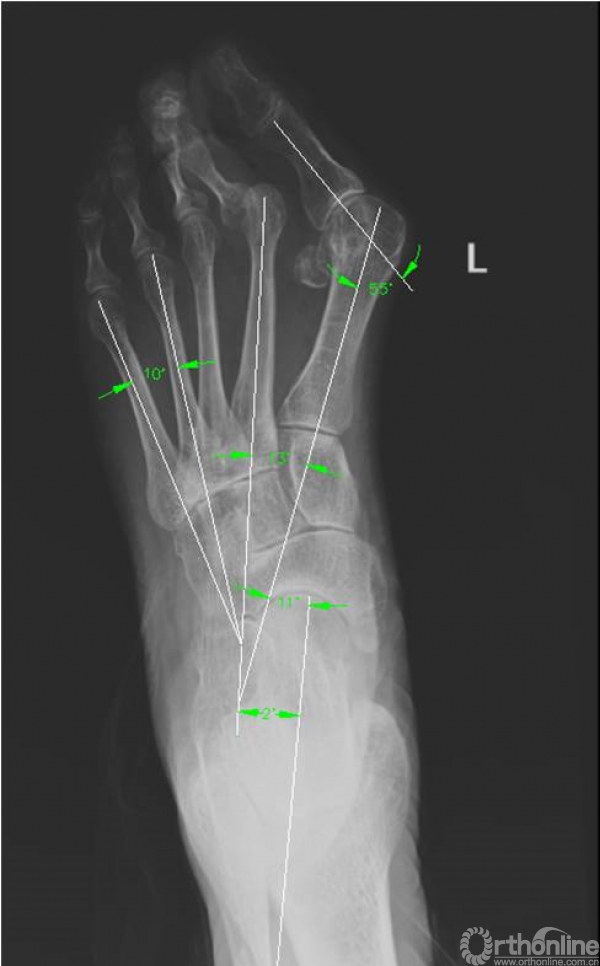

3. X线检查结果

X线检查